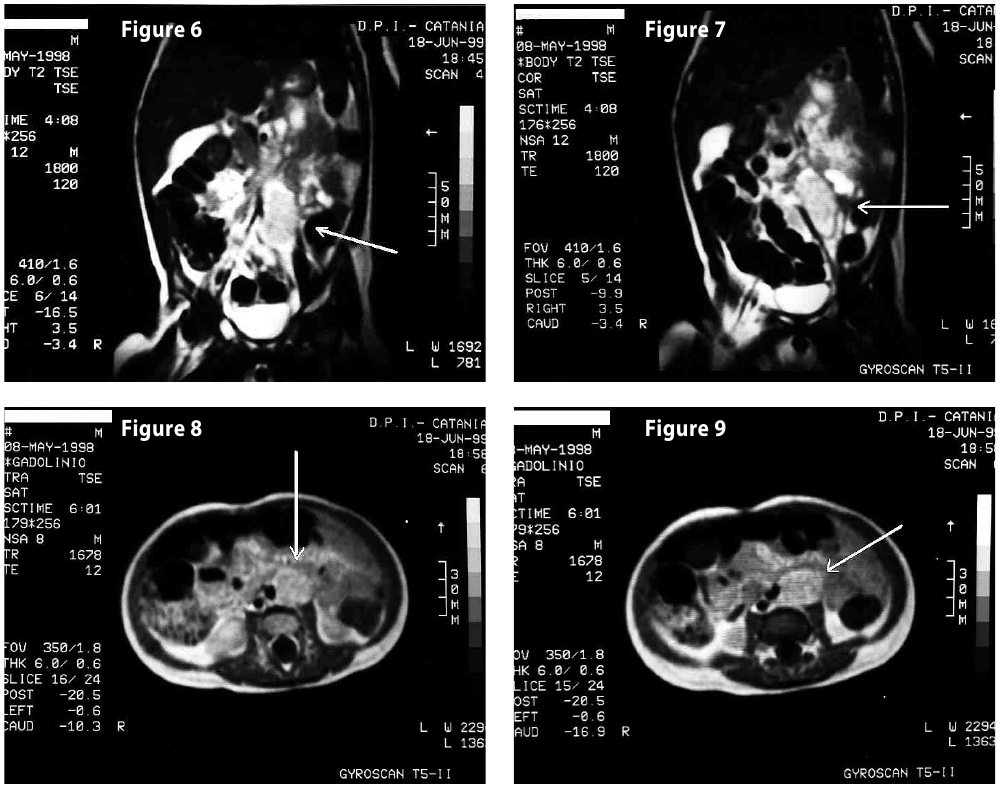

Complete objective response of neuroblastoma to biological treatment.

Figure6

Figure7

Figure8

Figure9